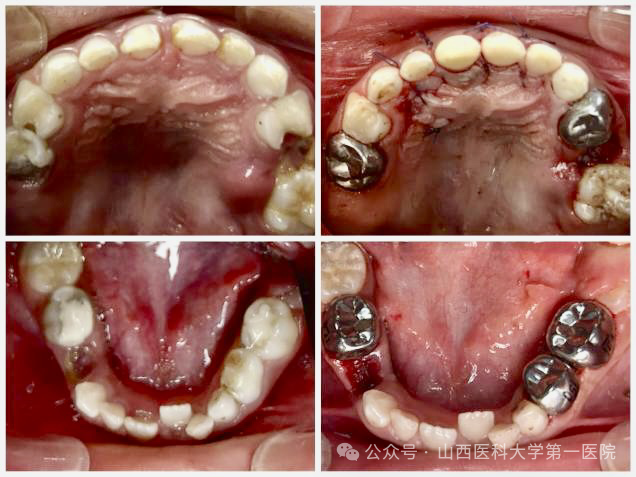

口腔内科儿童口腔团队在日间手术中心为一名6岁患儿在全麻下完成17颗牙齿的治疗,通过一站式精准干预解决了患儿复杂口腔问题,避免了多次治疗对患儿心理健康带来的不利影响。

儿童龋病患病率高达70%,很多患儿因龋齿出现牙痛、咀嚼困难、继承恒牙发育异常等问题,然而传统治疗常因患儿恐惧、哭闹或难以配合导致无法进行常规口腔治疗,若强制治疗可能因抗拒行为存在口唇牙龈软组织撕裂等。本次接受治疗的患儿因长期全口多颗牙龋齿导致乳牙严重缺损,伴牙髓炎症反复发作,同时影像学检查发现上前牙区存在2颗埋伏多生牙影响恒牙正常萌出,因患儿恐惧无法进行门诊治疗,口腔内科赵玮副主任医师、孟璐璐主治医师、杜晓红护士长、罗淋护士详细制定治疗方案,口腔颌面外科令狐清溪副主任医师全力配合,在麻醉科吕洁萍主任、侯瑜主治医师、日间手术中心护士长史丽萍的支持下,经三方会诊和全面评估在日间手术中心实施全麻下微创口腔治疗。

手术当天在麻醉科经鼻插管全气道管理全身麻醉下,口腔内科采用微创去腐复合树脂美学修复、牙髓根管治疗、牙髓切断术以及预成冠技术恢复患牙的形态及功能;口腔颌面外科团队微创拔除2颗埋伏牙多生牙,患儿术后2小时完全苏醒,经观察无任何不适于第二日上午离院。